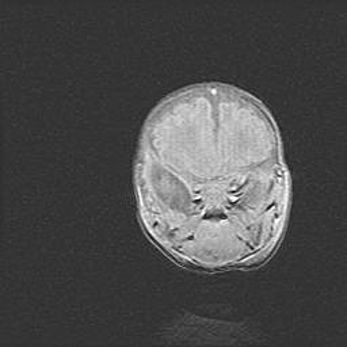

Лейкомаляция с кистозно-глиозной дегенерацией головного мозга.

Возраст: 2 месяца 25 дней

Вес: 6400 г

Окружность головы: 40 см

Срок гестации: 41 неделя

Лейкомаляцию относят к ишемически-гипоксическим повреждениям головного мозга, диагностируемым у новорожденных. При лейкомаляции в головном мозге обнаруживают очаги некроза, возникшие после тяжелой гипоксии и нарушения кровотока. В процессе морфогенеза очаги проходят три стадии: 1) развития некроза, 2) резорбции и 3) формирования глиозного рубца или кисты. Перивентрикулярная лейкомаляция (ПЛ) встречается примерно в 12% случаев среди новорожденных, обычно – у недоношенных детей, причем, частота ее зависит от массы, с которой младенец появился на свет. Наибольшее число малышей страдает лейкомаляцией, если масса при рождении 1500-2500 г.